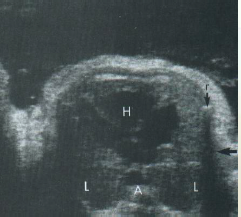

can you identify the fetal lt/rt sides?

also note the lung echotexture

sp is spine in trans

what does the T sign mean?

it rules out 90% of pathology

Left atrium lies closest to the fetal spine

Four chambers should be nearly equal in size

Right ventricular apex may appear thicker due to the presence of the moderator band

Foramen ovale flap into left atrium

Moderator band (AKA septomarginal trabecula in right ventricle). thick muscle.

Foramen Ovale (thin white arrow pointing down)